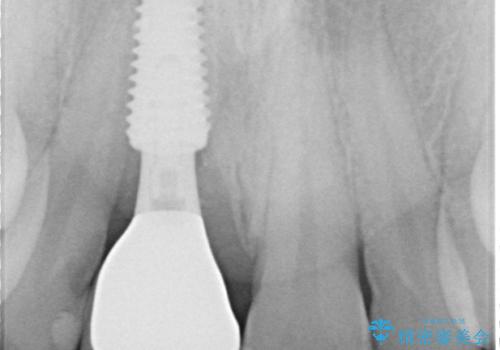

- 外れるたびに接着剤で応急処置を施してきた前歯のインプラント治療を希望して来院された患者様です。

以前から治療が必要であることは認識されていましたが、海外から日本に移住された1週間後に前歯が脱離したことで、当院でのインプラント治療を選択されました。

度重なる脱離により、表側の炎症が非常に強くなっており、歯を支える骨が失われている状態でした。